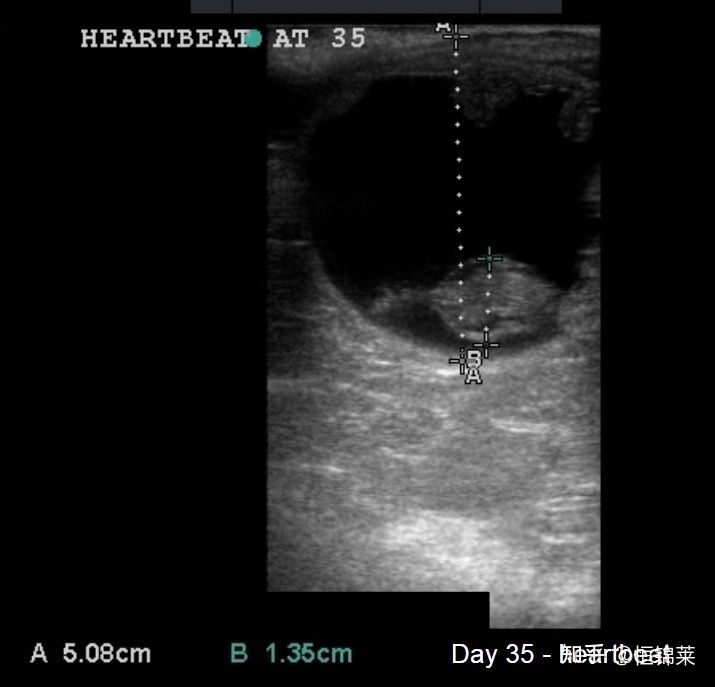

在对母马进行超声检查以检测怀孕期间,我们将寻找胚胎囊泡。这是在超声屏幕上看到的黑色球体,代表早期胚胎内的液体和胚胎和/或胎儿周围发育中的胎盘内的液体。您可以在下方看到第 12 天和第 19 天母马的超声波扫描结果。注意囊泡的形状是如何变化的。

兽用B超仪检测马妊娠超声图像